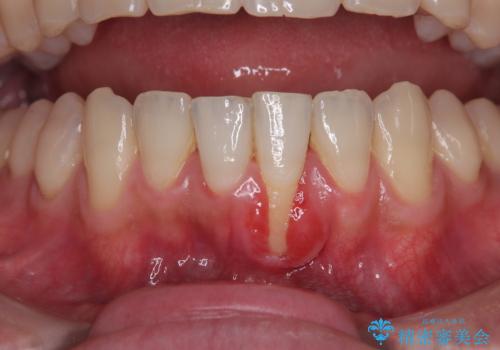

- 他院で矯正治療を終えた結果、下顎前歯の歯肉が退縮してしまい、歯根が見えていることが気になるとのことで来院された患者様です。

歯肉退縮に対して、上顎からの結合組織移植術(CTG)により、歯根の被覆を行うとともに、歯肉の厚みを増すことで将来の退縮リスクを抑制することとしました。